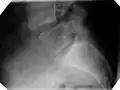

| X-ray of the lateral lumbar spine with a grade III anterolisthesis at the L5-S1 level | |

X-ray of measurement of spondylolisthesis at the lumbosacral joint, being 25% in this example

X-ray picture of a grade 1 isthmic anterolisthesis at L4-5

X-ray of a grade 4 anterolisthesis at L5-S1 with spinal misalignment indicated